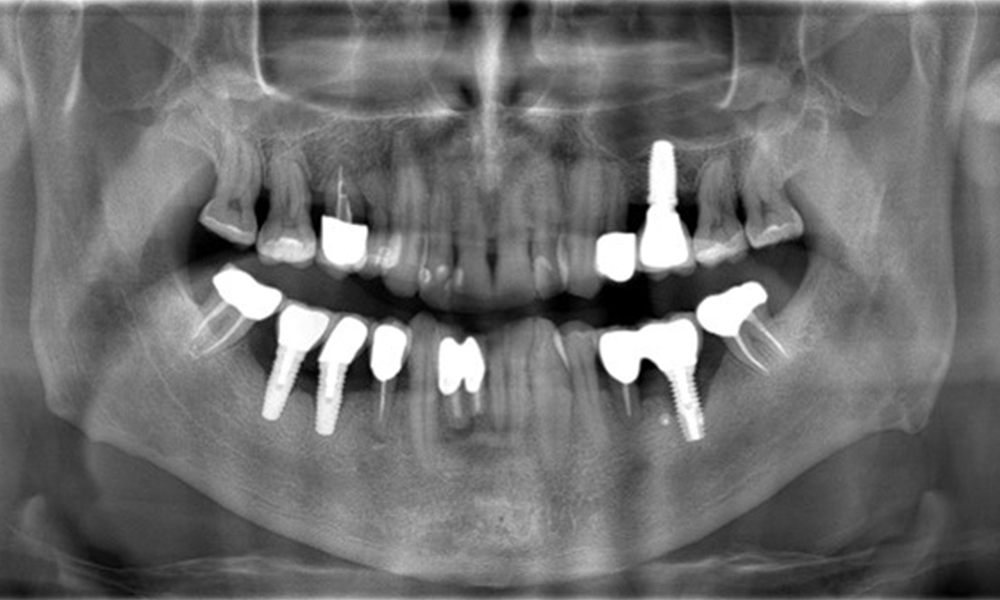

Röntgenaufnahme zeigt Verlauf des Knochenabbaus

"Die Röntgenaufnahmen zeigen den Verlauf des Knochenabbaus. OPG vom 29.06.2020 (links) und OPG vom 26.02.2024 (rechts)